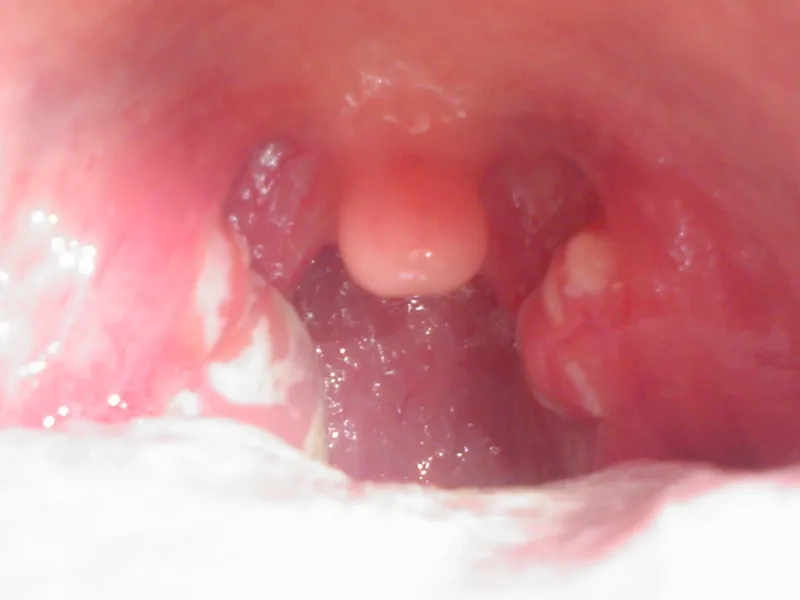

• Look for red, swollen tonsils, sometimes with white patches or streaks of pus, and tiny red spots (petechiae) on the roof of the mouth.